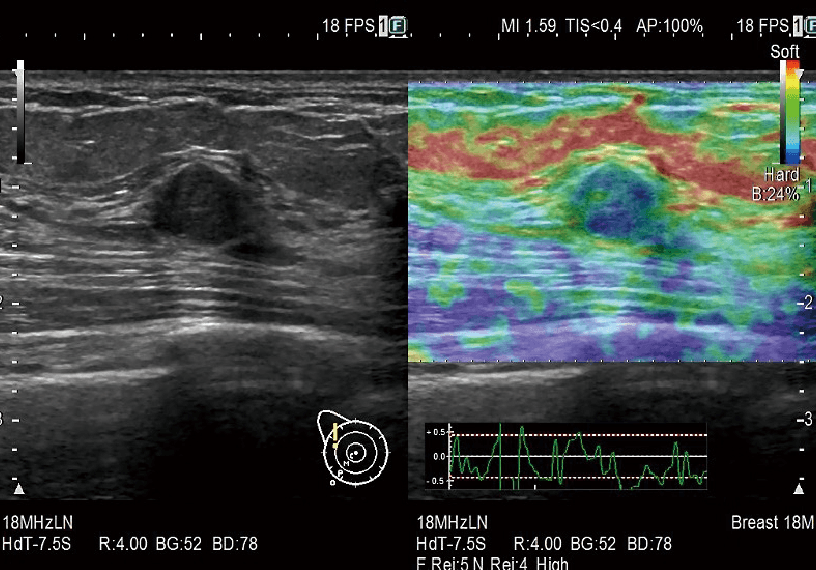

Gerçek Zamanlı Doku Elastografisi (RTE)

RTE, doku gerinimini gerçek zamanlı olarak değerlendirir ve doku sertliğini renk haritası olarak görüntüler. Uygulama, meme de dahil olmak üzere çok çeşitli klinik alanlarda doğrulanmıştır ve karaciğer fibroz evrelemesinin tahmini elastisite değerini hesaplamak mümkündür.